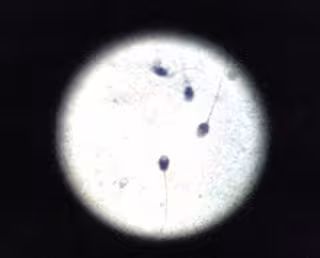

Espermatozoides, semen

Especialistas médicos de Ginefiv, clínica centrada en el tratamiento de la esterilidad y la infertilidad, recuerdan que hay estudios que prueban que la exposición continuada al calor podría provocar en el varón diferentes anomalías. Entre ellas destacan la astenoszoospermia, alteración en la movilidad de los espermatozoides, o la oligospermia, que se origina al descender la cantidad de espermatozoides en la eyaculación, a consecuencia del incremento térmico en el escroto, tejido que envuelve y recubre los testículos.

A partir de los 35 grados la calidad del semen desciende y el número de espermatozoides desciende significativamente, incrementándose la fragmentación de ADN de los espermatozoides, parámetro relacionado con la capacidad fecundante del esperma y que incluso se ha relacionado con un incremento en la tasa de abortos.